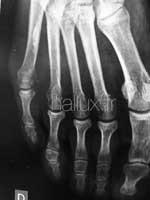

CETTE OSTEOTOMIE METATRSIENNE

PEUT ETRE REALISÉE EN PERCUTANÉ.

par une incision puctiforme, de 3 à 5 mm. On utilise pour sectionner l'os,une fraise motorisée, très fine avec un moteur rotatif tournant à vitesse lente (500 à 2000 tours/minute) pour éviter la brûlure des tissus. L'ostéotomie et le recul de la tête du métatarsien, est de façon encore mois aggressive.

Les cicatrices sont alors minimes.

Ces incisions sont pratiquées dans des zones anatomiques précises, à distance des structures nerveuses et tendineuses et permettent d'y associer des gestes tendineux et sur les parties molles.

Le geste chirurgical est guidé par une appareil de radsiocopie (amplificateur de brillance).